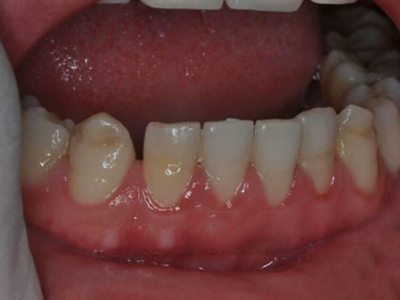

牙齿

坑

牙釉质发育不全牙表面上有坑图

牙釉质发育不全发展到严重时,导致牙釉质表面缺损,表现为带状、窝状的褐色凹坑,容易积存食物残渣诱发龋齿,表现为牙齿边上出现深褐色小洞。